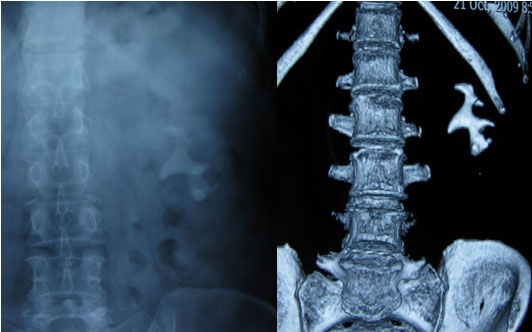

经皮肾镜治疗鹿角形结石

实现泌尿系结石的微创综合治疗